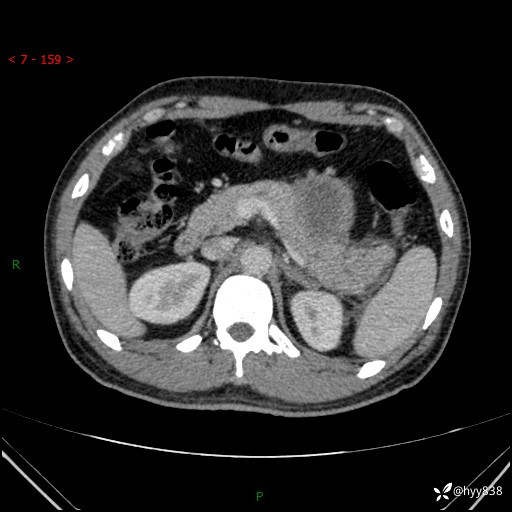

病例39岁/女,左侧腰痛入院。腹腔囊实性肿块,定位、定性---结果公布~

性别:男

年龄:39岁

简要病史:左侧腰痛待查,CT发现腹腔占位

腹部CT平扫+增强